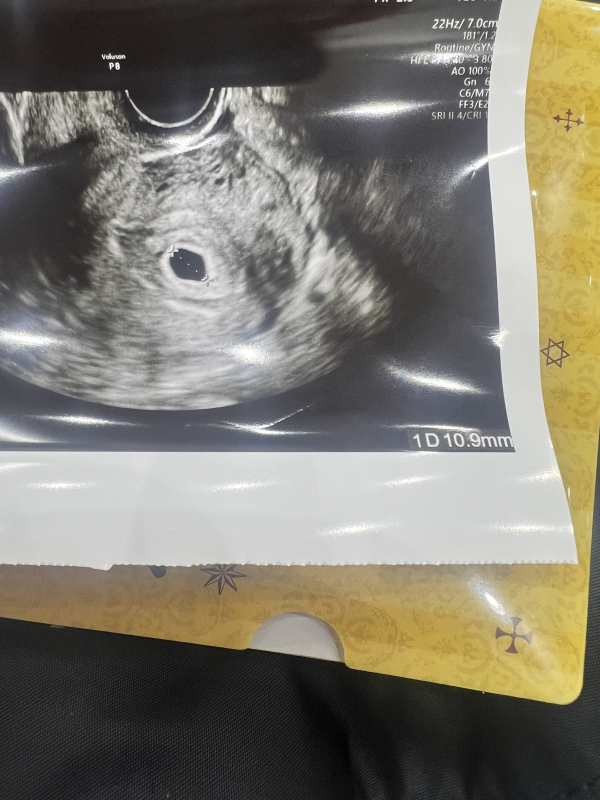

はじめまして、体外受精で2人目を授かり現在5週6日目の妊婦です。5週3日目に生理2日目ほどの出血と何回か血の塊が出ました。次の日には生理終わりかけの出血、それ以降は茶おりになりましたがまだ微妙に出ています。最初に出血したのがクリニックだったのでエコーしてもらい、胎嚢が13ミリでしたが今日の受診で10ミリでした。(先生には上記の説明をしてエコーしてもらいました)先生に小さくなっていることを質問しても「そうですか?機械の角度とかもあるので」と言われましたが本来はもっと成長していると思うのでとても不安です。もらった写真には胎嚢のみでしたがエコー中は卵黄囊と胎芽らしきものは写っていました。出血の跡なのか血腫なのか、胎嚢横に影はありました。 6週間近ですが心拍確認できなかったのも気になっています。胎嚢が小さくなると流産の兆候なのでしょうか?茶おり以外腹痛はなし、つわりは気持ちわるさが見られます。お返事お待ちしております。

胎嚢の大きさについては、機械の当たる角度などによって多少の誤差は出てくると思いますので、小さくなっているというわけではないかもしれません。週数からみても胎嚢が小さいわけではないかなと思いますので、流産の兆候とは考えにくいかなと思います。心拍についても、週数からみてまだ確認できない場合もあるかと思います。